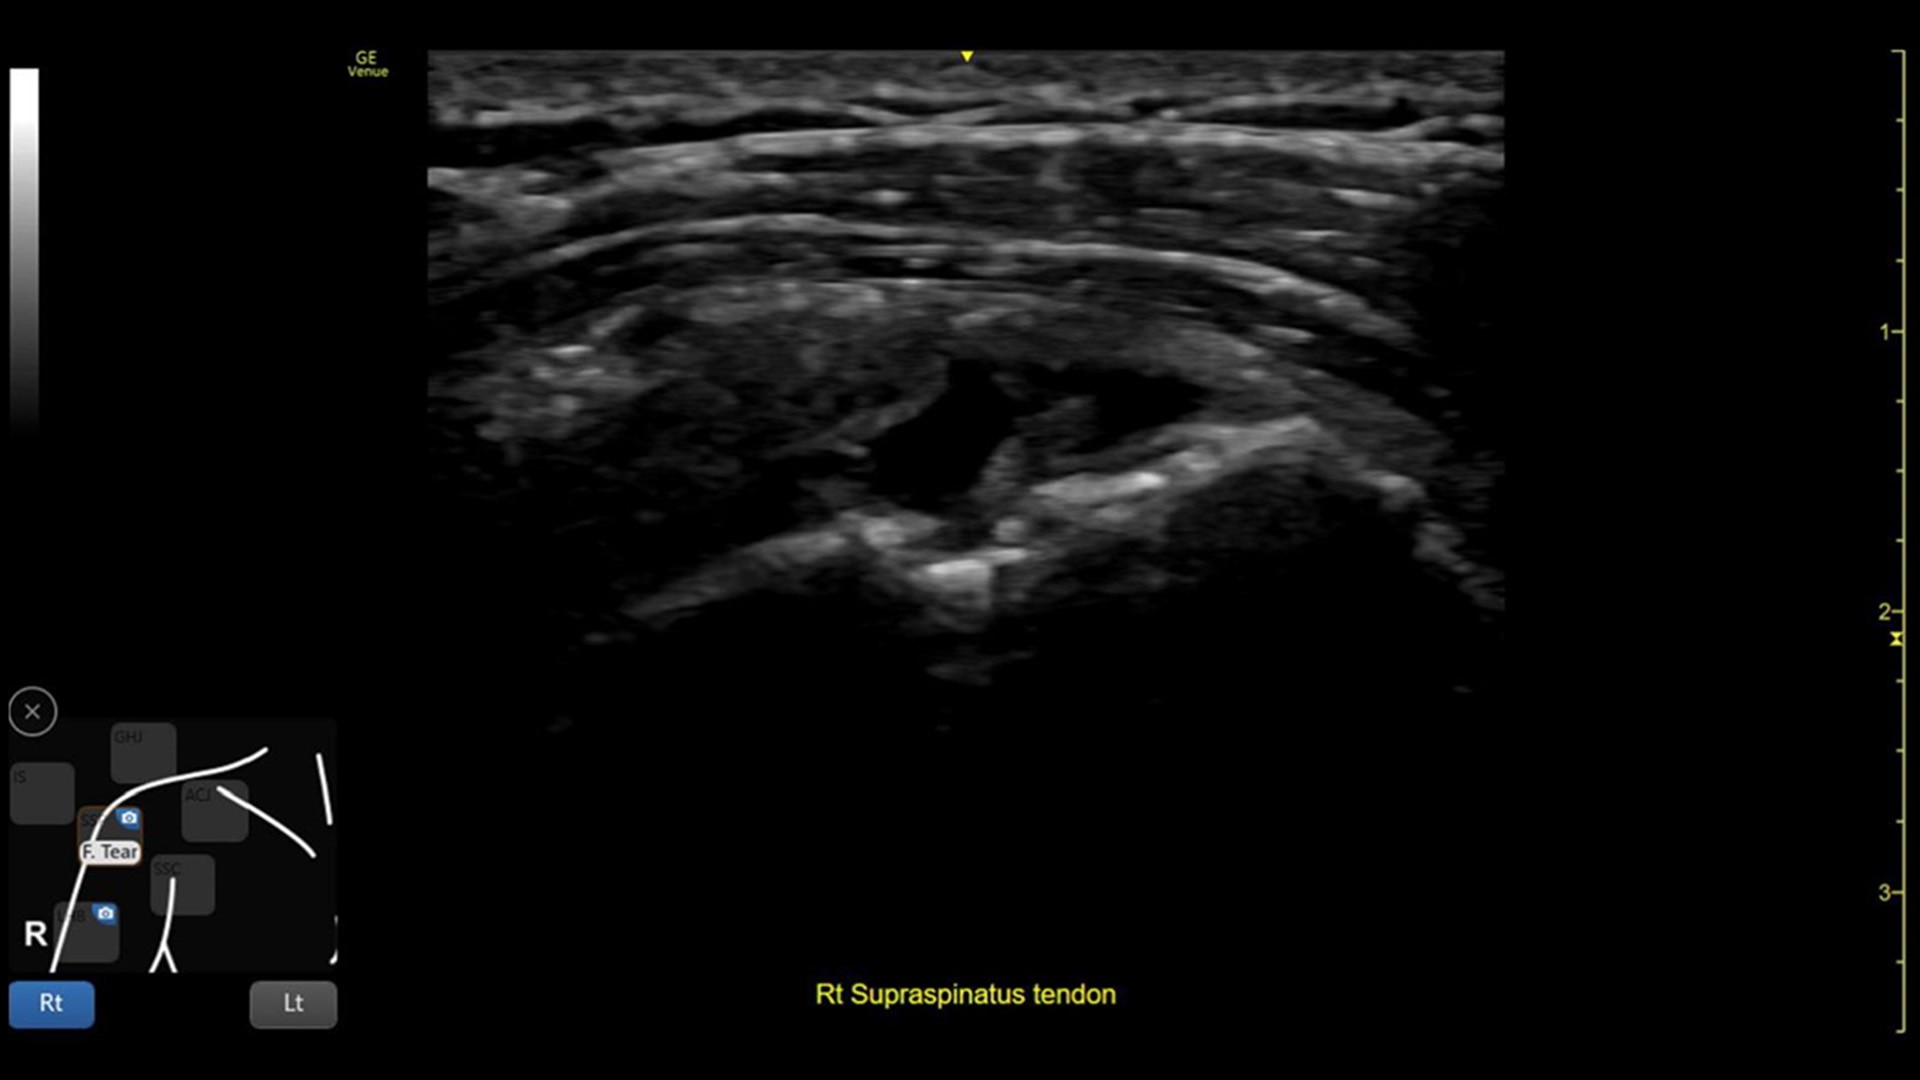

Excellent visualization with Needle Mode

Needle Mode also allows you to easily differentiate between the needle and patient anatomy with confidence—allowing you to quickly guide the needle exactly where it needs to be and helping to minimize patient discomfort.